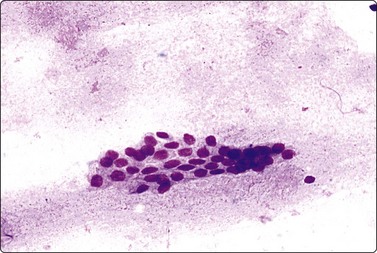

Fig. 7.1 Radiation-induced atypia

(A) The epithelial cells in this irregular cluster show considerable nuclear enlargement, pleomorphism and hyperchromasia, but also some degenerative changes such as loss of nuclear structure (MGG, HP); (B) Corresponding tissue section (H&E, IP).